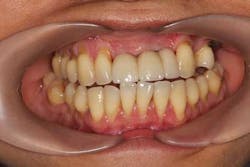

Fig. 15